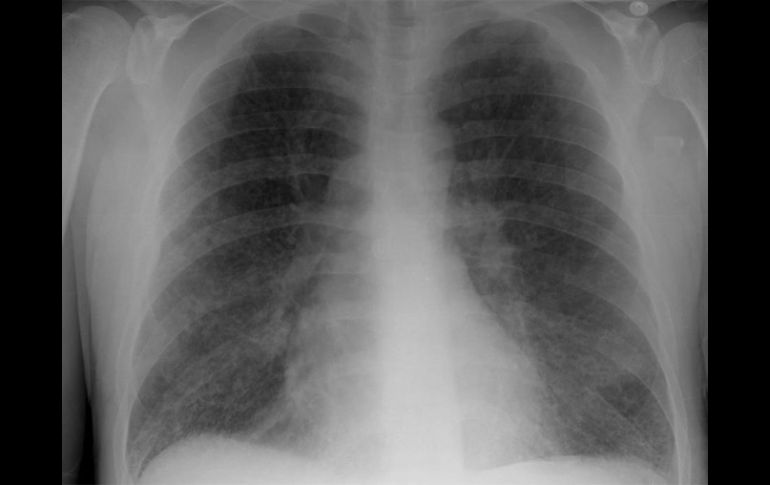

Tecnología | En el país se han registrado ocho mil 255 nuevos casos de esta enfermedad Factores ajenos al tabaquismo relacionados al cáncer de pulmón La exposición a algunas sustancias químicas o una alimentación inadecuada, también pueden causar el cáncer Por: EL INFORMADOR 7 de enero de 2011 - 17:15 hs Lo más recomendable es que el médico de primer contacto aconseje al paciente acudir con un neumólogo. ID / CIUDAD DE MÉXICO (07/ENE/2011).- En México se han registrado ocho mil 255 nuevos casos de cáncer de pulmón, de los cuales la mayoría tienen en común al tabaquismo como elemento clave de incidencia. Sin embargo, un importante porcentaje de personas afectadas por esta enfermedad aseguran no haber probado cigarrillo alguno en su vida, lo que apunta a otros factores en la predisposición a desarrollar este padecimiento, entre los que figura la exposición a algunas sustancias químicas o una alimentación inadecuada. Este tipo de información, así como ayuda al paciente, es la que pretende brindar la asociación civil de reciente creación Respirando con Valor, que busca difundir al público y afectados datos sobre tratamientos, estadísticas y opciones referentes al cáncer pulmonar. Al ahondar en los factores que conllevan al desarrollo de la enfermedad, la licenciada Patricia Mondragón, vocal esa asociación civil, explicó que existen factores tales como la genética, la inhalación del humo de leña o la exposición continua al arsénico, cromo, níquel o asbesto, además de tener deficiencia de vitamina A, C o E, los que pueden influir en la aparición del cáncer pulmonar; y estos factores representan el 48 por ciento de las causas del padecimiento en no fumadores. Además indicó que existen dos tipos principales de cáncer pulmonar, el de células pequeñas y no pequeñas. Algunos síntomas que pueden presentar las personas con cáncer de pulmón son: tos que empeora con el tiempo, dolor en el pecho, hemoptisis (flemas con sangre), disnea (silbido en el tórax), ronquera, pérdida de peso, fatiga e hinchazón de cuello y de cara. Es necesario que quien presente alguna de estas señales acuda al médico para tener un diagnóstico temprano, “el problema es que por lo general el cáncer de pulmón no se detecta en sus primeras fases, ya que suele confundirse fácilmente con males menores” indicó Patricia Mondragón. “Lo más recomendable es que el médico de primer contacto aconseje al paciente acudir con un neumólogo (especialista en los pulmones) cuando los síntomas persistan por más de tres meses”, advirtió. El primer estudio a realizar cuando existe sospecha de esta enfermedad es una radiografía, pero en algunos casos será necesario realizar una tomografía por emisión de positrones, que consiste en inyectarle a la persona un medio de contraste que ayudará a visualizar el crecimiento anormal de las células y su extensión. Además de los métodos tradicionales de radioterapia (empleo de rayos X), quimioterapia (administración de sustancias químicas) y cirugía, en la actualidad existe otro tratamiento de nueva generación llamado “terapia blanco” que ayuda y mejora la calidad de vida del paciente, evitando los efectos secundarios (pérdida de cabello, nausea, vómito, diarrea o estreñimiento, anemia, por mencionar algunos) de las terapias normales, ya que sólo incide en las células cancerígenas y evita dañar el sistema inmune. Para finalizar, la vocera de Respirando con Valor apuntó que es importante que las personas expuestas a los factores de riesgo se realicen un chequeo anual, de esta manera podrá ser detectado en sus primeras etapas y tendrá más opciones de tratamiento además de una mejor calidad de vida. Con información de la Agencia ID. Temas Ciencia médica cáncer de pulmón Enfermedades Lee También Julieta Fierro será homenajeada en la FIL INAPAM: ¿Cómo solicitar un turno para consulta médica gratuita? Octubre Rosa: ¿Cuánto cuesta una mastografía en Jalisco según Profeco? Nobel de Química premia el desarrollo de estructuras metal-orgánicas Recibe las últimas noticias en tu e-mail Todo lo que necesitas saber para comenzar tu día Registrarse implica aceptar los Términos y Condiciones